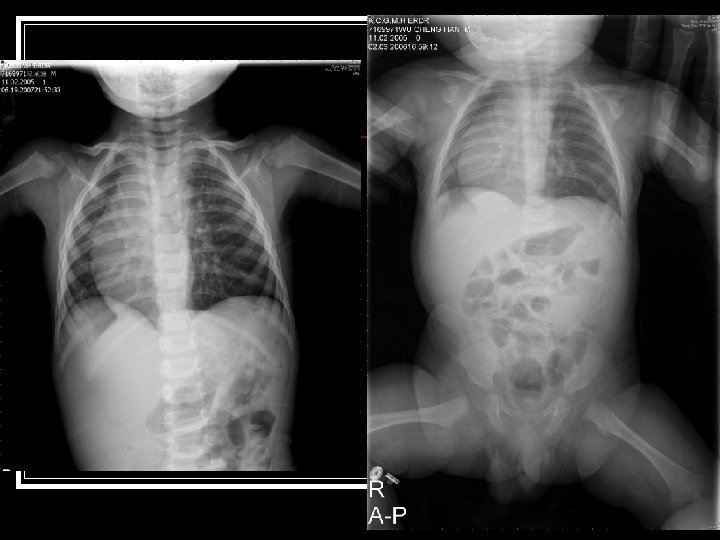

Pediatric case Conference 吳小弟 n 病歷號: 7169971 n 生日: 94/11/02 n 就診日期: 96/6/19 (1 y 7 m/o) n TPR: 36. 6/130/21 n CC:Fever for 2 days n

Ped. 2 -D echo (2007/3/12) n n n n n Ao (mm): 15 LA (mm): 15 LVEDD (mm): 32 LVESD (mm): 18 EF: 78 % Dextroposition of heart. (Whole heart shift to right side of spine, apex pointed to left side) Normal intracardiac structural relationship. No pericardial effusion. Good ventricular performance. Vmax 0. 9 m/s for main pulmonary artery. No significant mitral and tricuspid regurgitation. No VSD, no PDA. 2. 9 mm atrial septal defect, secundum type. Normal left-sided aortic arch. Vmax 1. 0 m/s for ascending aorta Vmax 1. 3 m/s for descending aorta. Descending aorta at left anterior aspect of spine. Right-sided superior vena cava. Inferior vena cava at right anterior aspect of spine.

Hospital Course (6/25 -28) 3 D CT of chest performed on 6/25 n There is narrowing of the trachea in the level of aortic arch with narrowest diameter about 0. 25 cm about 1. 2 cm in length n There is dextrocardia with left side aortic arch n There is double SVC with left SVC drainage to coronary sinus n